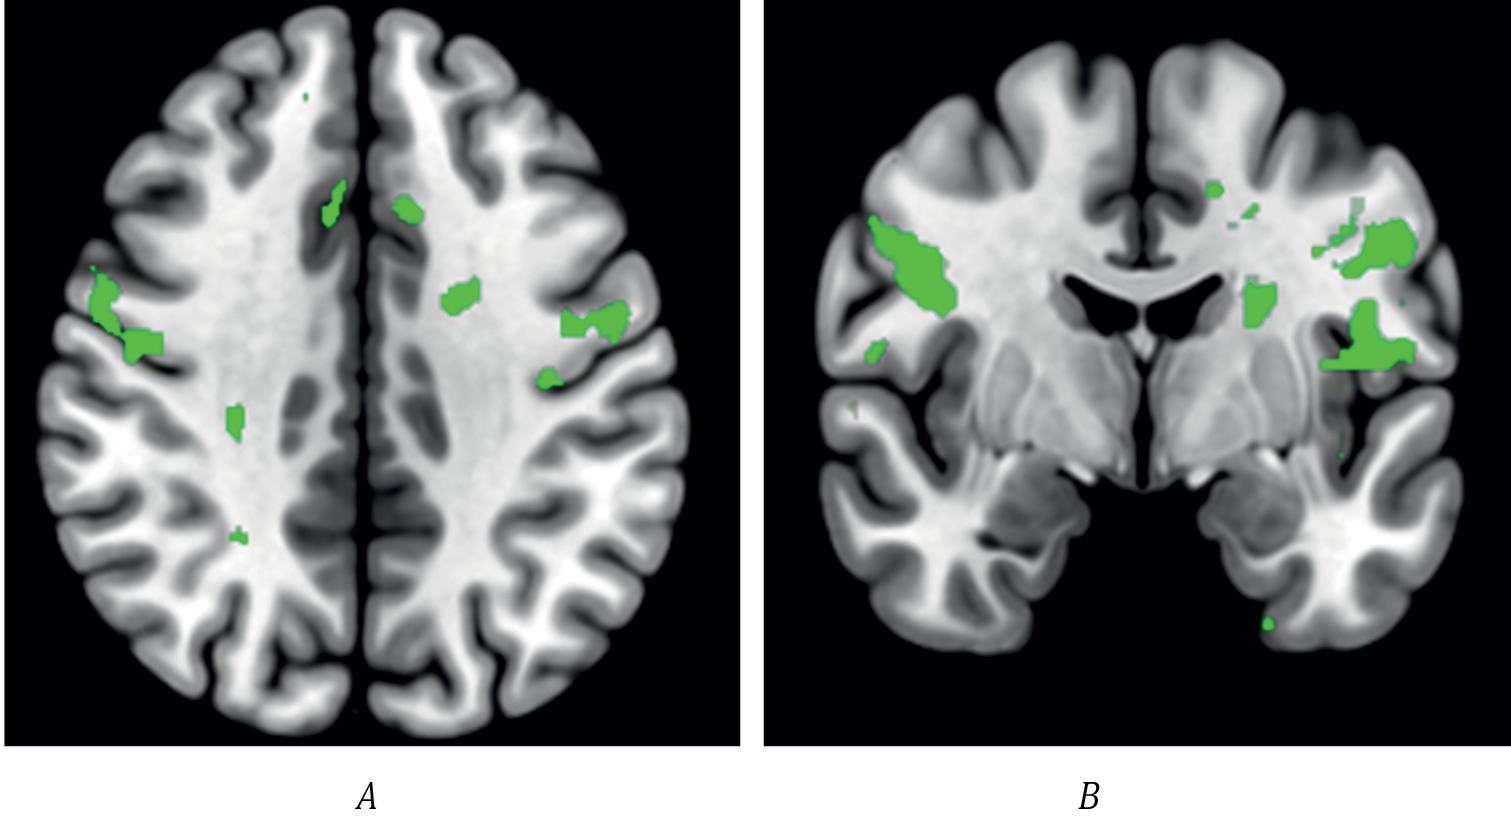

Сахарозаменители (аспартам, сукралоза, стевия, эритрит) предлагаются как более здоровая альтернатива сахарозе и фруктозе. Однако их влияние на мозговую активность и поведение человека остаётся предметом дискуссии. Некоторые исследования показывают, что сахарозаменители могут не активировать системы вознаграждения как углеводы, что может влиять на чувство насыщения и потребление пищи в дальнейшем. В контексте ожирения фМРТ используется для оценки функциональной нейрональной активности, участвующей в регуляции энергетического обмена и метаболизма. В Научном центре неврологии получены пилотные результаты сравнения эффектов сахарозы и сахарозаменителя с применением фМРТ, которые показали различия в активации в области дополнительной моторной и дорсолатеральной префронтальной коры среди здоровых добровольцев (рис. 2).

Рис. 2. Внутригрупповое сравнение активации головного мозга здоровых испытуемых при визуализации пищевой парадигмы (изображения аппетитной и неаппетитной еды) после приёма сахара и сахарозаменителя. На срезах головного мозга представлены зоны с отличающейся активацией. После приёма сахара отмечается бóльшая активация в дополнительной моторной и дорсолатеральной префронтальной коре с обеих сторон.

А — аксиальная проекция; В — коронарная проекция.